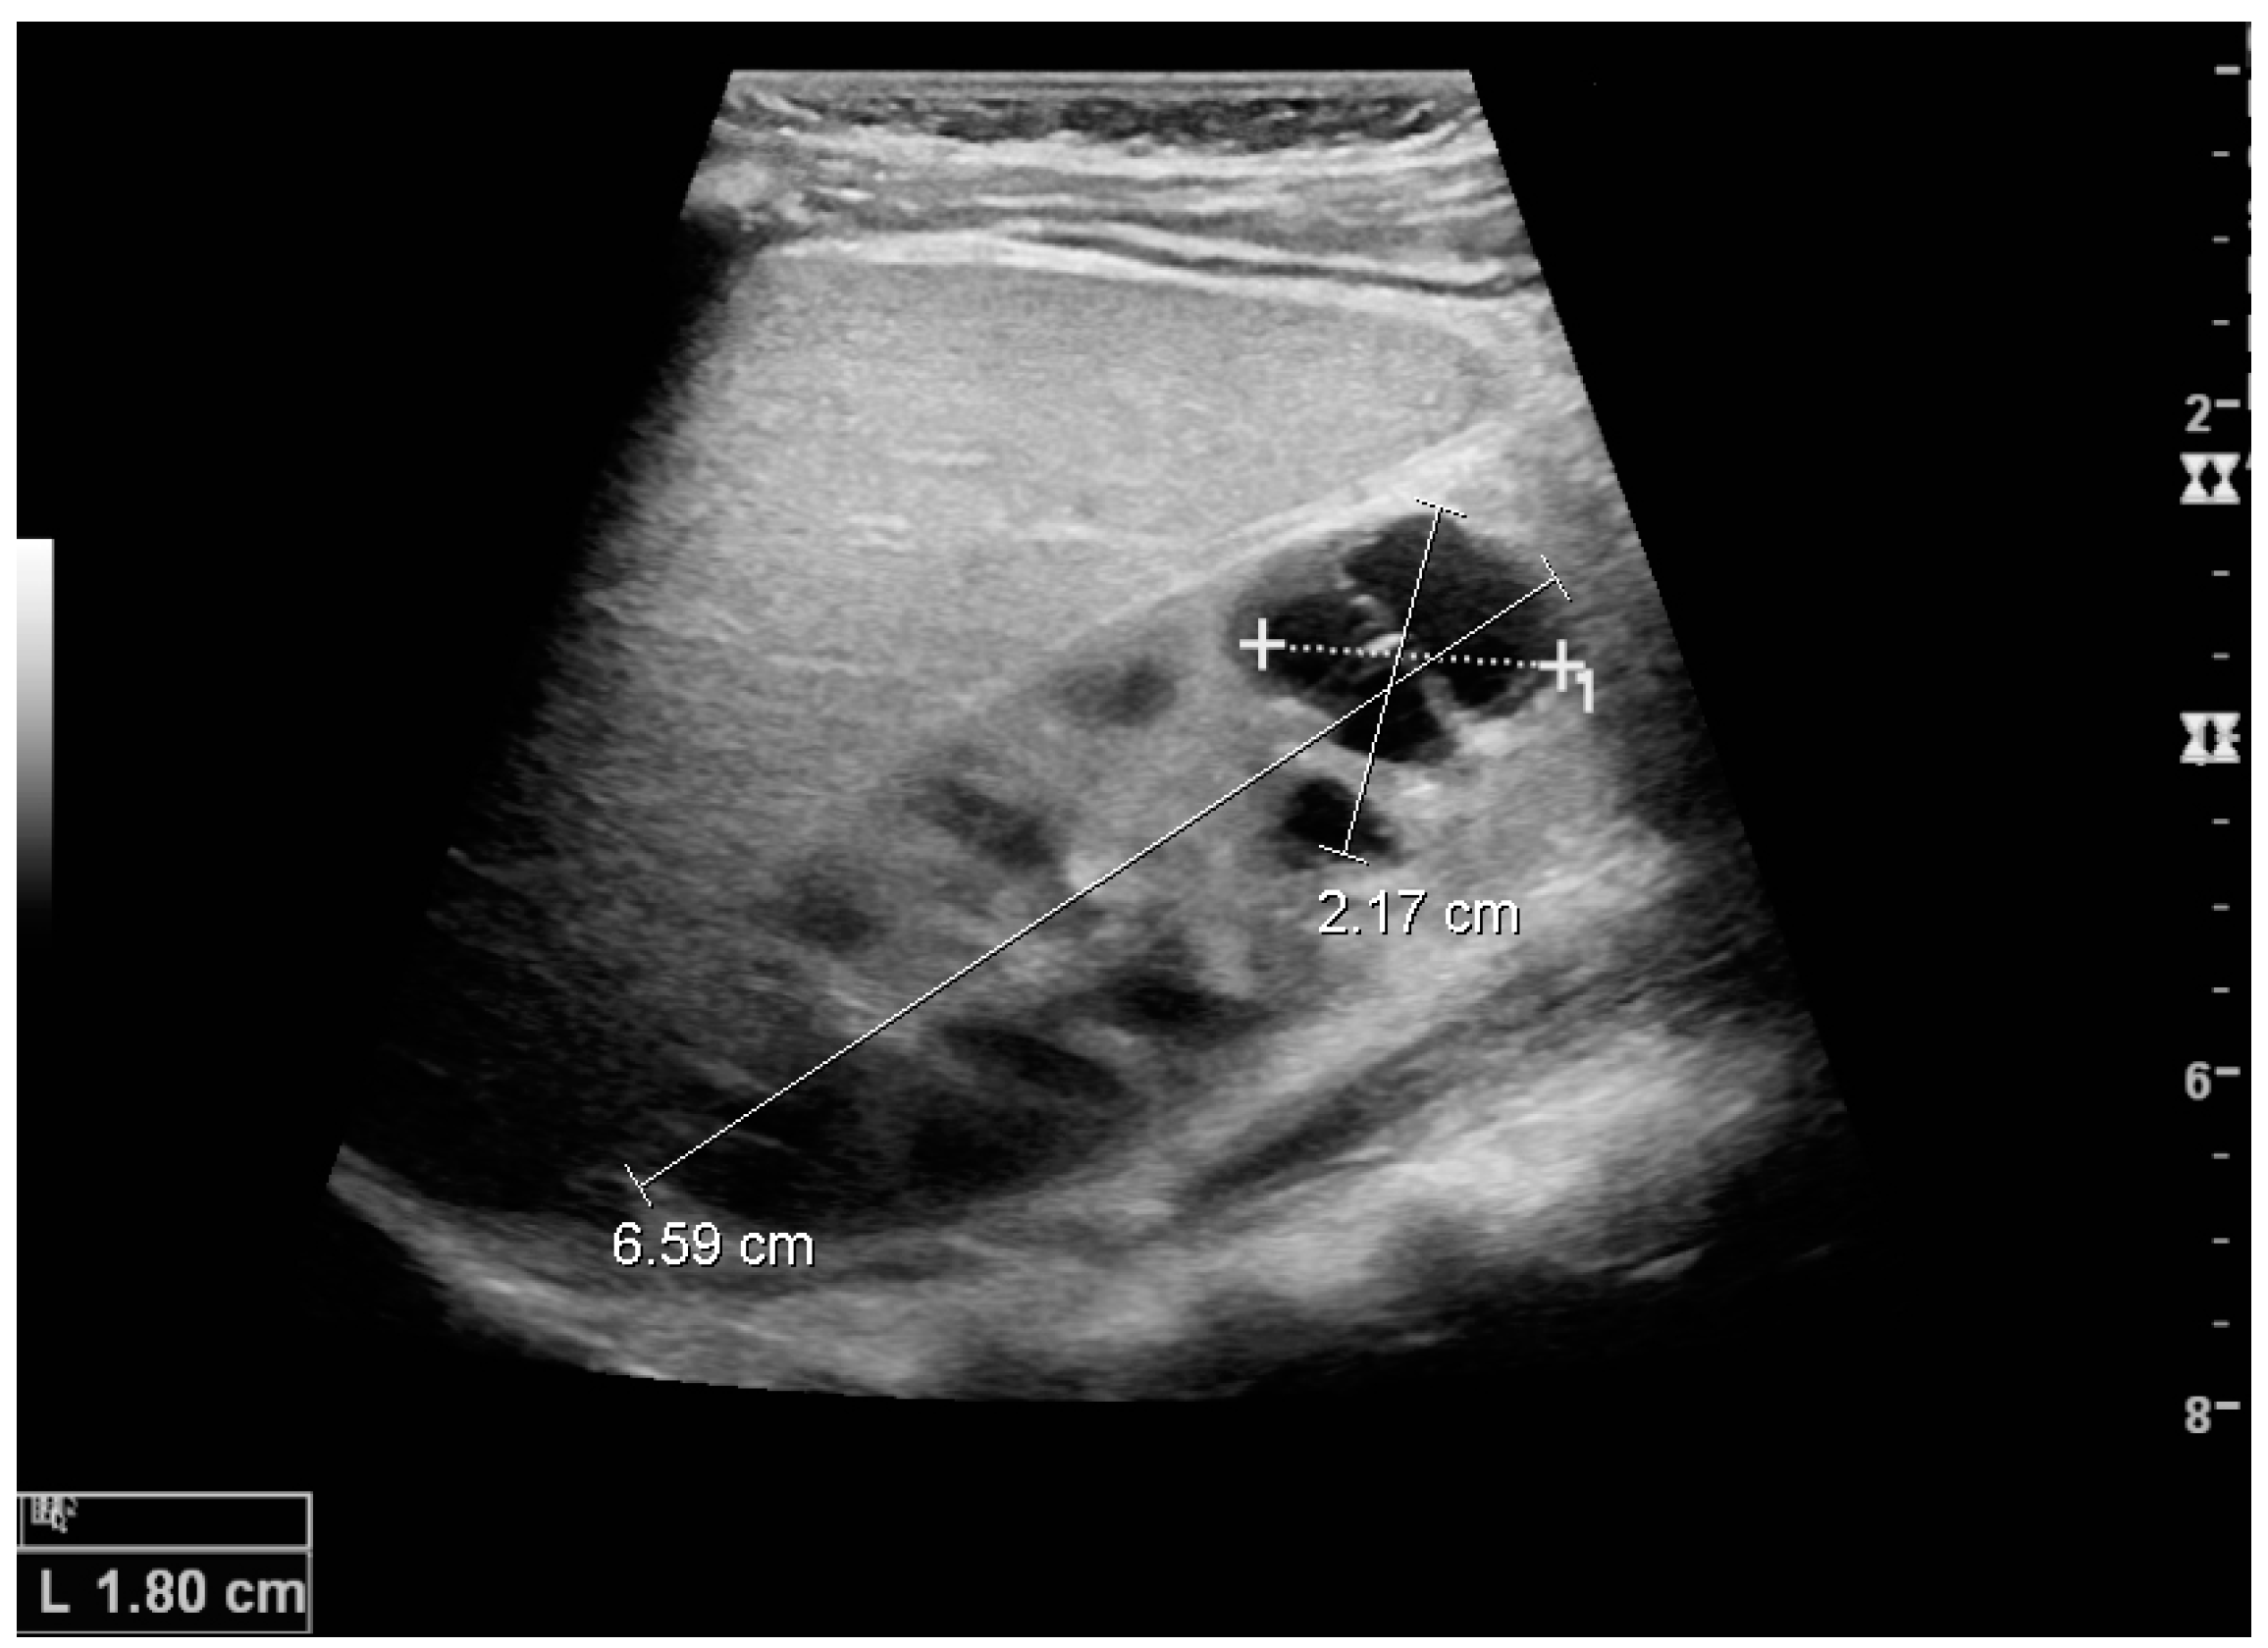

Figure 16. Hydronephrosis with dilated anechoic pelvis and calyces, along with cortical atrophy. The width of a calyx is measured on the US image in the longitudinal scan plane, and illustrated by ‘+’ and a dashed line.

Figure 17. Same patient as in Figure 16 with measurement of the pelvis dilation in the transverse scan plane illustrated on the US image with ‘+’ and a dashed line.